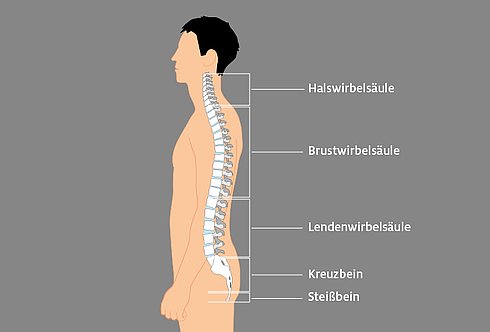

:background_color(FFFFFF):format(jpeg)/images/article/de/wirbelsaule/a1wjCWbEAeBhCqqodBbjHQ_Wirbels_ule_von_dorsal.png)